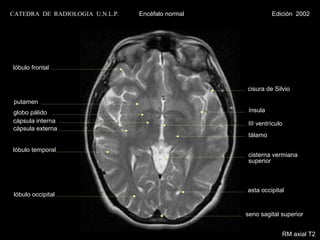

CATEDRA DE RADIOLOGIA U.N.L.P.   Encéfalo normal             Edición 2002

lóbulo frontal

cisura de Silvio

putamen

globo pálido                                        ínsula

cápsula interna                                     III ventrículo

cápsula externa

tálamo

lóbulo temporal

cisterna vermiana

superior

asta occipital

lóbulo occipital

seno sagital superior

RM axial T2